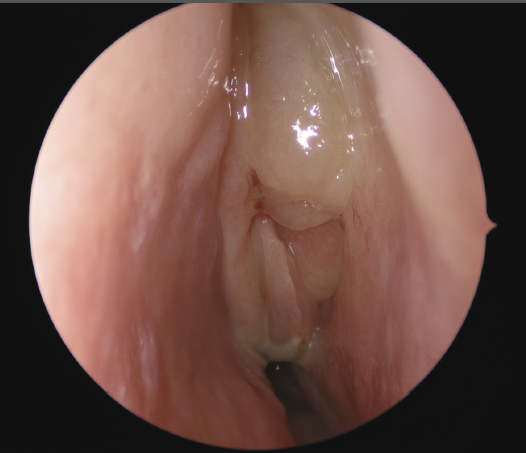

Image of inside the nose viewed with help of a inserted camera

Chronic rhinosinusitis afflicts over 30 million patients in the USA annually, or roughly 12.5% of the population. It has tremendous impacts on the economy and on a patient’s quality of life.  It is defined as symptoms of sinonasal inflammation lasting at least twelve consecutive weeks with corresponding objective physical findings. Symptoms may include nasal obstruction, congestion, nasal drainage, post-nasal drip, facial pressure, loss of smell and/or taste, fever, fatigue, and dental pain. To examine for sinonasal inflammation your physician will use a nasal endoscope to evaluate your nasal cavities and paranasal sinuses. You may also undergo computed tomography (CT) or another form of imaging.

Image of nasal endocopesThere are many causes of chronic rhinosinusitis and the specific cause in any one patient is likely multifactorial. Contributors to the disease process may be environmental, anatomic, congenital, immune, or infectious in nature.

Medical management is typically the primary treatment approach for chronic rhinosinusitis and may include saline nasal irrigations, intranasal corticosteroid sprays, antibiotics, systemic corticosteroids, and allergy pills. If medical treatment fails, endoscopic sinus surgery is the next step in management. The goals of surgery are to reestablish drainage pathways for the paranasal sinuses with large openings that allow the delivery of irrigations and topical medications. The routine postoperative course consists of regular nasal endoscopies to debride the postsurgical sinus cavities and to ensure proper healing.